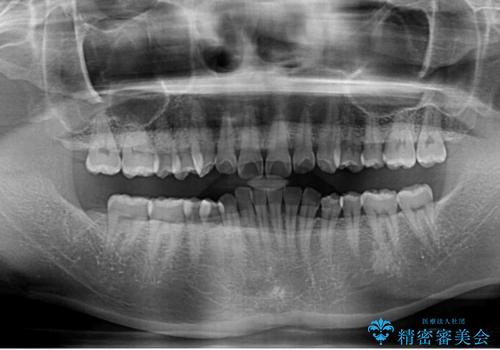

- 下顎前歯が完全に隠れてしまっていることを気にして来院された患者様です。

下顎の臼歯が手前に傾斜していることで咬み合わせが深くなってしまい、下顎前歯が見えないほどに上顎前歯が覆い被さっている状態でした。

下顎臼歯を起き上がらせるためにユーティリティーアーチを使用し、一気に深い咬み合わせを改善することができました。